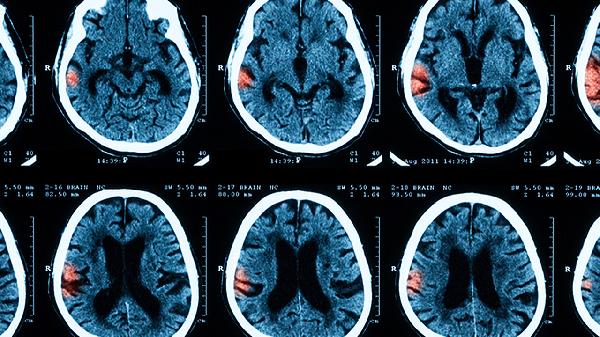

5、意识障碍:意识障碍可能表现为嗜睡、烦躁、昏迷等,严重时可能伴有抽搐或惊厥。此时需立即就医,进行神经系统评估和影像学检查。治疗包括抗感染、降颅压、镇静等综合措施,以控制病情进展。

病毒性脑膜炎的诊断主要依据临床表现、脑脊液检查、影像学检查和病原学检测。典型症状包括发热、头痛、颈项强直,脑脊液...